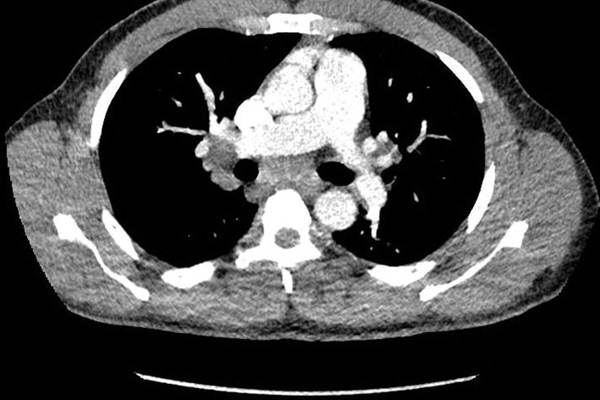

An unusual presentation of sarcoidosis